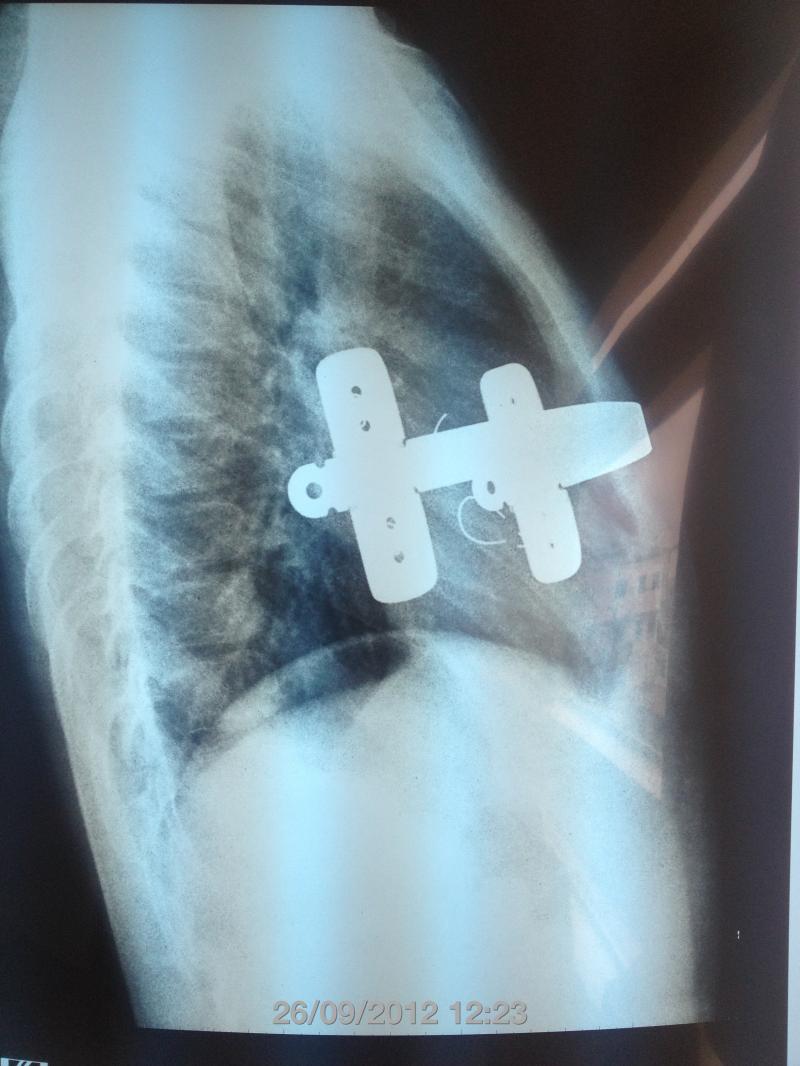

Barra colocada a la Abramson, para corrección de PECTUS CARINATUM LATERAL.